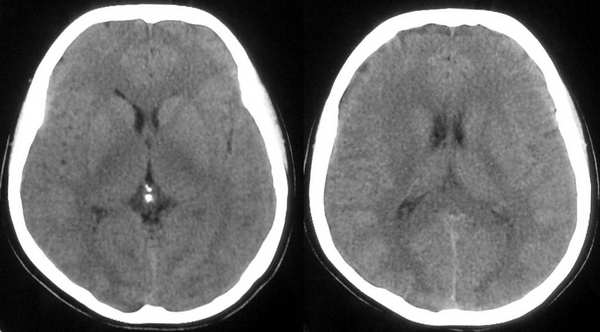

患者,女,32岁,时有头晕,无恶心呕吐。

左侧放射冠区是不是有灰质异位啊

这个病例为正常的头部ct表现,只是由于摆位不正而造成了诸多疑问,所以在工作中要注意摆位问题。

我认为是正常的颅脑影像。左侧颞顶叶脑组织示略高密度结构是近外侧裂区的正常皮质结构,不是灰质移位。由于摆的位置不正,左侧的脑组织较右侧的低一个层面。